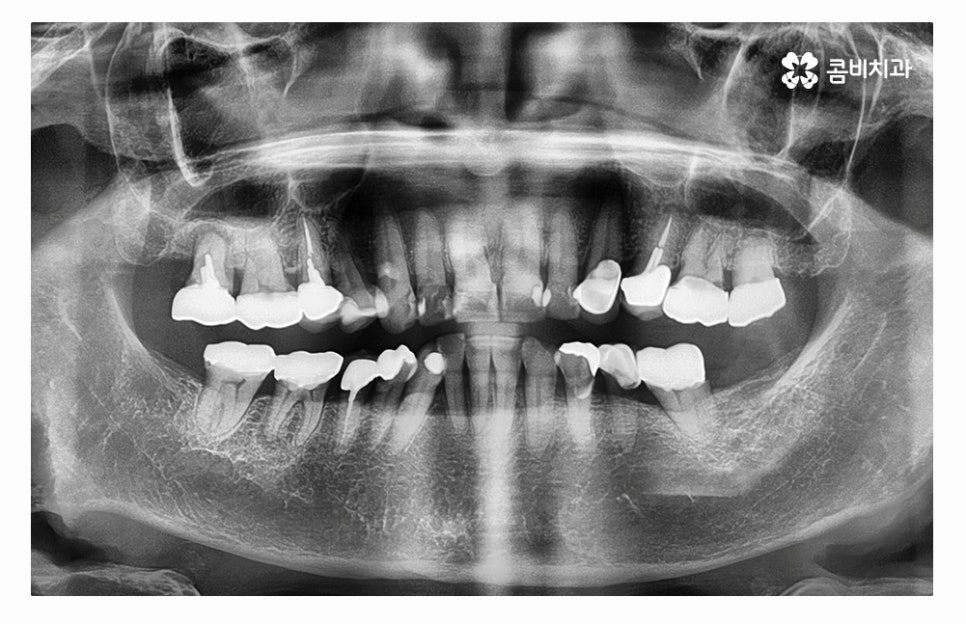

오늘 소개드릴 사례의 경우 충치로 인해 치아를 잃게 되었으며

발치 후 임플란트 수술을 통해 치아의 기능을 수복하였는데

치아를 잃게 되었을 때 원인을 잘 찾고 반복된 문제가 발생하지

않도록 정확한 진단이 필요하다고 할 수 있어요.

어금니는 저작기능에서 주된 기능을 하기도 하지만

사랑니와 밀접하고 치아 사이에 이물질이 끼거나

치석이 쌓이기 쉽기 때문에 충치가 발생하기 쉬운 부위이며